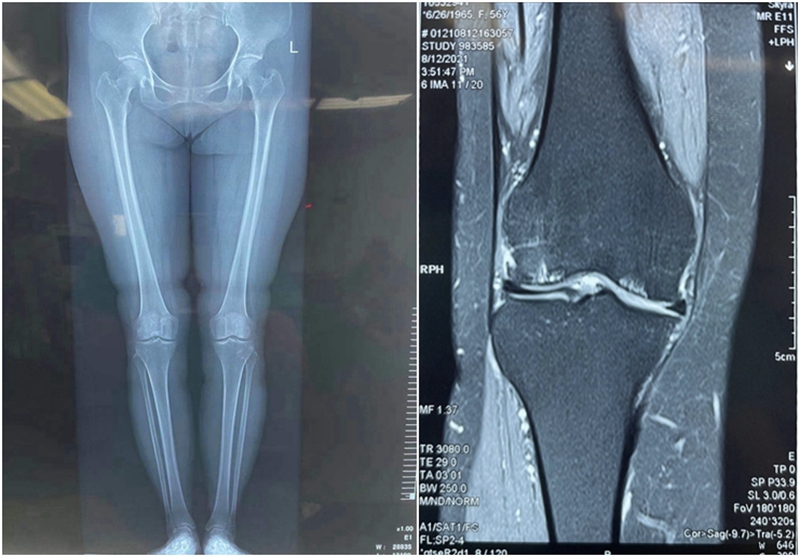

患者女性,56岁,右膝关节疼痛,X线显示关节间隙基本正常,整体力线轻度内翻畸形,关节内游离体,核磁显示内外侧软骨病变,内外侧半月板完整。由于担心外侧软骨退变,门诊计划行单纯关节镜清理,取游离体。不做截骨术减压内侧病变。

术前再次阅片

MR显示外侧负重区良好,外侧软骨磨损位于非负重区